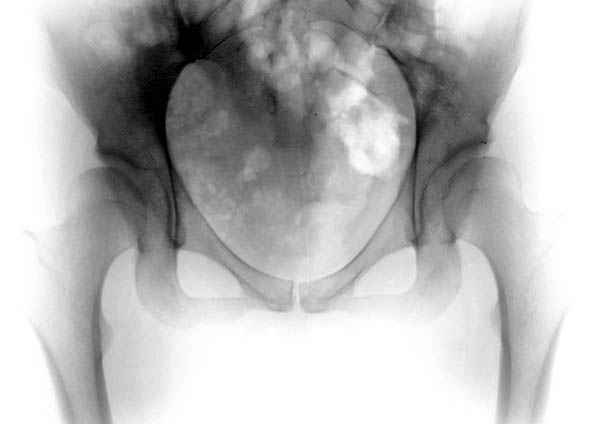

Картина типичной эволюции дисплазии сустава "кистовидная перестройка", на фоне неправильного взаймоотношения сустава "да тут угол Виберга 0 градусов" на вершине наибольшей нагрузки в вертлужной впадине образовался участок разрежения, "киста", в последующем через этот участок образуется перелом - стадия фрагментация дисплазии.

Для установки диагноза достаточно информации, на рентгенограмме передний и задний край ацетабулум образовали перекрест, "цифру восемь", указывающий на небольшую ретроверсию, а суставная щель одинаковой ширины на всем протяжении, что доказывает, что с покрытием хряща проблем нет. Головка бедра покрыта всего наполовину, это явное нарушения взаимоотношений.

Кстати, после остеотомии и удаления нагрузки от проекции кист в нашей серии были самостоятельное выздоровление кисты и зарастание фрагментированного участка стенки кисты даже после минимальной фиксации.